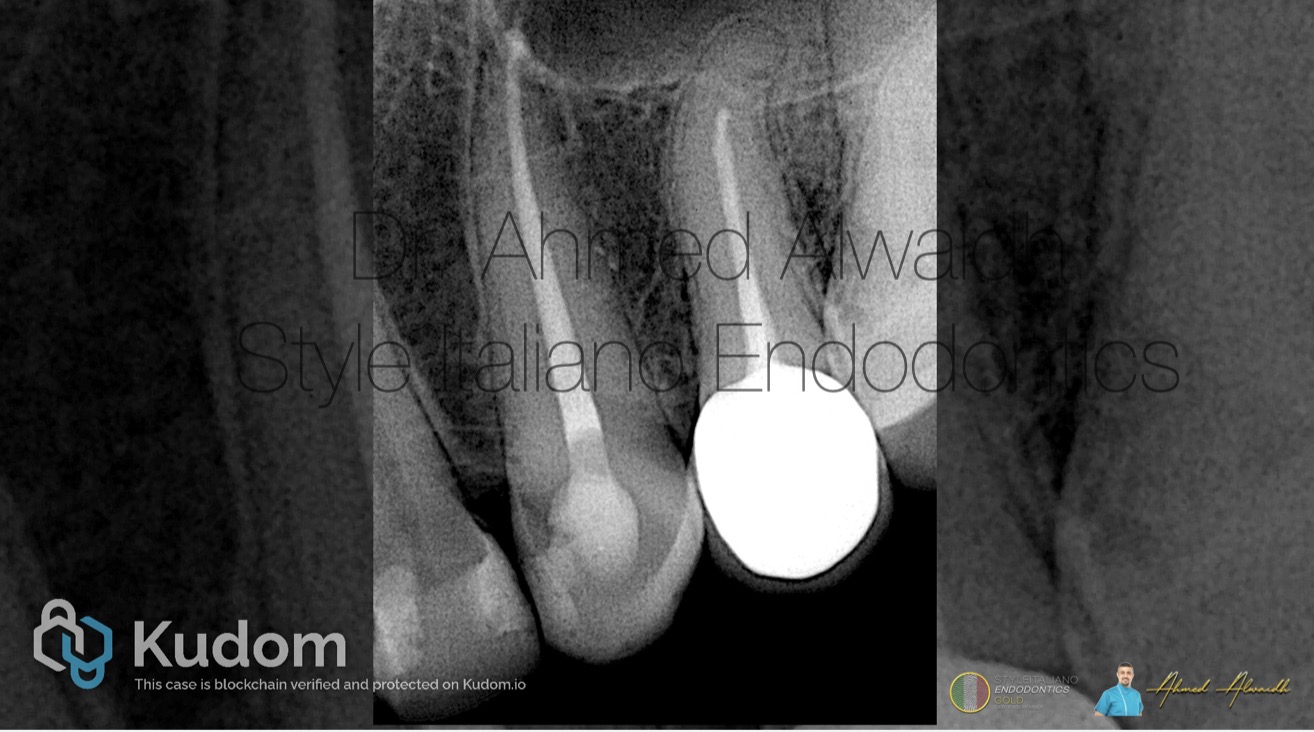

Fig. 2

Cone beam CT confirmed the presence of peri apical changes around the apex of UL3